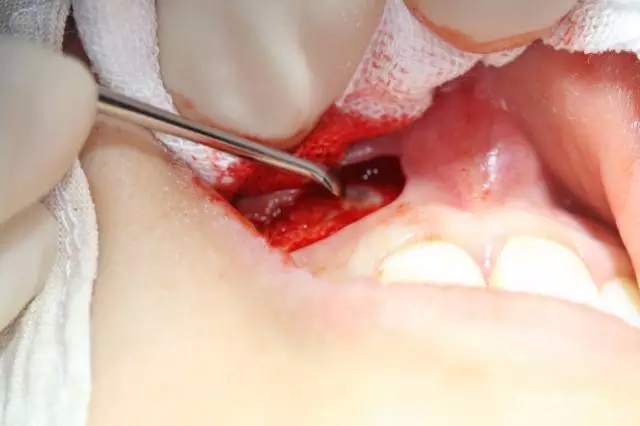

病例資料: 患者、柴xx、女、16歲。??茩z查及病歷如下圖: 患者同意我院正畸科建議,遂轉(zhuǎn)診倒外科。術(shù)前簽知情同意書。 治療過程: 圖1.術(shù)前的CBCT檢查:13阻生,疑為含牙囊腫??v剖面顯示12牙根吸收至根尖1/3。 圖2.局部麻醉下 。行唇側(cè)弧形切口,12松動(dòng)不到1°。 圖3.翻瓣、暴露骨面。 圖4.去骨、 暴露13牙冠 圖5.去骨、逐漸顯露13。 圖7.拔除13. 圖8.摘除囊壁 圖9.必須完整剝離囊壁。 圖10.摘除囊壁后形成的骨腔 圖11.超聲骨刀12根尖倒預(yù)備 圖13. 消毒棉球骨腔內(nèi)隔濕血液,紙尖干燥倒預(yù)備好的根管 圖14. 紙尖無血即可 圖15。MTA倒充填 圖16.骨腔填塞膠原蛋白海綿 圖17.拔除的13及摘除的囊壁 圖18.縫合 圖19.術(shù)后x線根尖片影像:MTA封閉根尖